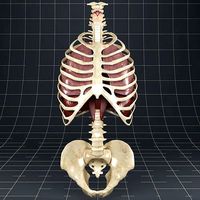

Bone Anatomy 3D Model

...bone anatomy 3d model thoracic animation internal organs torso cervical medical bone anatomy 3d model download .c4d .max .obj...

Human Bone Anatomy 3D Model

...bone anatomy 3d model medical animation internal organs torso cervical thoracic human bone anatomy 3d model download .c4d .max...

Human Thoracic Vertebrae3d model

...vertebrae3d model cgstudio human thoracic vertebrae middle vertebral ligament cervical pelvis spinal cord skeletal system anatomy people ribs segment...

Human Thoracic Vertebrae 3D Model

...model 3dexport digitallab3d human thoracic vertebrae middle vertebral ligament cervical pelvis spinal cord skeletal system anatomy people ribs segment...